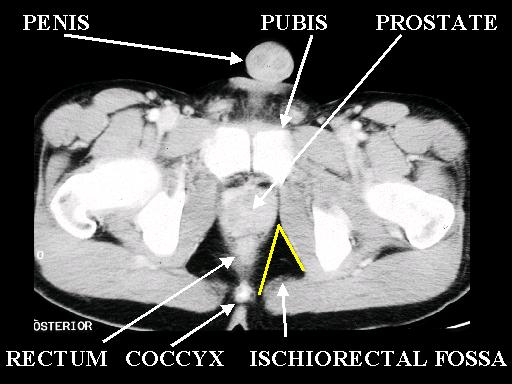

MS 204 MALE PELVIS 2